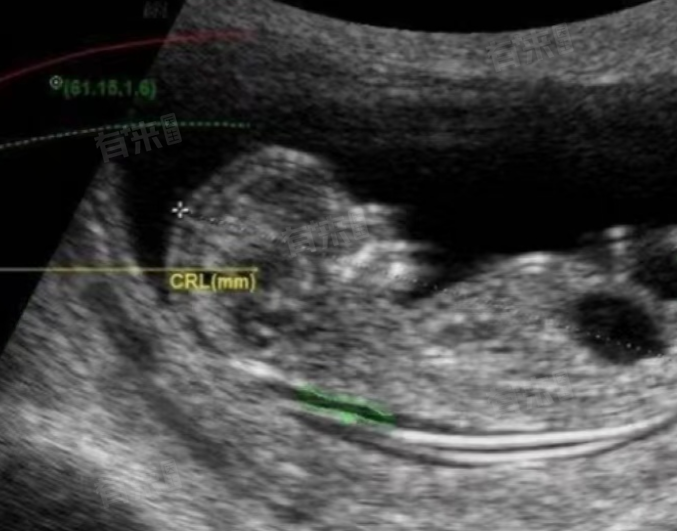

- NT检查,即颈项透明层检查,是通过超声波扫描胎儿颈部透明组织的厚度,来预测胎儿是否存在某些染色体异常的风险,如唐氏综合征等。这一检查通常在孕11-13周+6天进行,此时胎儿已经发育到一定大小,B超能够清晰显示其结构。

- 憋尿通常用于孕早期(如孕6-8周)的B超检查,以帮助医生更清晰地看到孕囊和胚胎。然而,在孕11-13周+6天进行NT检查时,胎儿已经足够大,膀胱充盈与否对检查结果的影响已经微乎其微。因此,孕妇在进行NT检查时,无需特意憋尿。